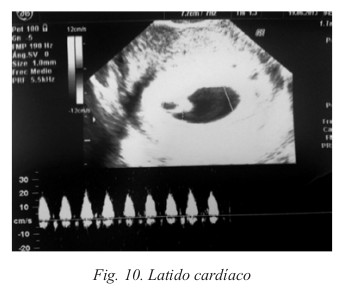

Entre las semanas 4 y 6 aparece la vesícula vitelina. En este momento es posible visualizar el embrión de 2-5 mm de tamaño y detectar la vitalidad del feto mediante el latido cardíaco (Tabla 15). El latido cardíaco es posible detectarlo en la sexta semana, mediante sonda vaginal; mientras que por vía abdominal se suele detectar en la séptima semana (Fig. 10).